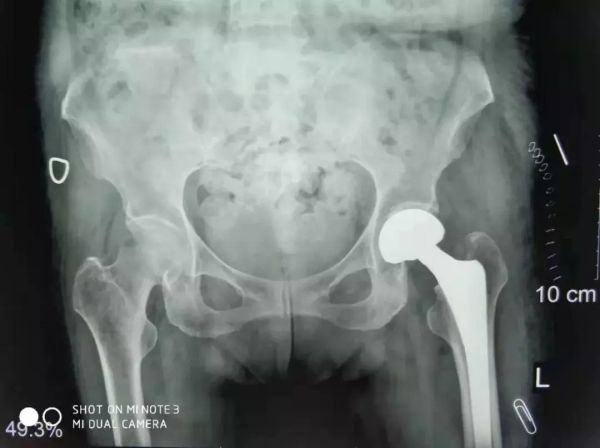

關(guān)節(jié)科羅軍主任和易觀俊主治醫(yī)師聯(lián)合麻醉科、內(nèi)科、超聲科專家集體會診及評估,并確定了最佳手術(shù)方式和麻醉方案,并積極做好充分的術(shù)前準(zhǔn)備。于是,11月2日在危立軍副院長帶領(lǐng)手術(shù)團(tuán)隊(duì)按照術(shù)前的討論方案,在腰部麻醉下行人工股骨頭置換,手術(shù)僅用了20分鐘。

患者股骨頭置換手術(shù)照片